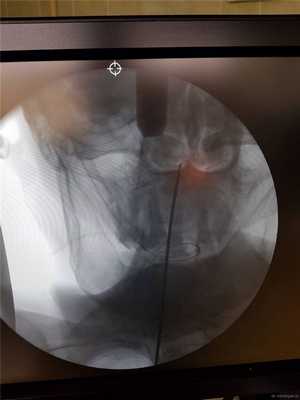

Контроль в прямой проекции.

Спица проводится дрелью до верхушки С2. Затем так же проводится и вторая.

Затем первую спицу можно удалить и на ее место закрутить винт с двойной резьбой, предварительно измерив длину необходимого импланта по шаблону.

Вкручивается второй винт.